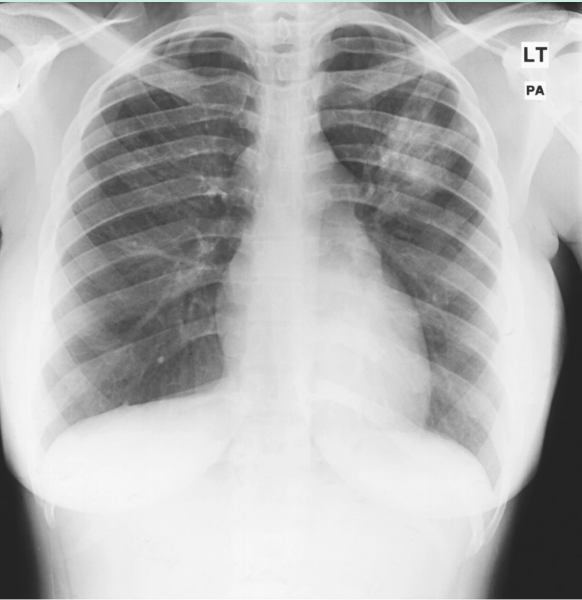

结核病(TB)在监狱囚犯中常见。一名囚犯出现结核病症状后,感染控制小组进入监狱。囚犯咳嗽,体重减轻,出汗。胸片显示正常组织破坏,提示肺结核(Fig 23.6)。

Fig 23.6 胸片显示了肺结核的典型改变,这些改变往往会影响到肺尖。左肺上部的混浊清晰可见。

她的痰培养结果呈结核分枝杆菌阳性,证实了诊断结果。患者被转移到监狱医院接受治疗,并防止她感染其他患者。